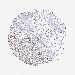

KIDNEY RENAL CLEAR CELL CARCINOMA (TCGA) - Interactive survival scatter ploti

ENOPH1 is potential prognostic, high expression is favorable in Kidney Renal Clear Cell Carcinoma (TCGA)

: 26.07

Average pTPM 32.8

Number of samples 521